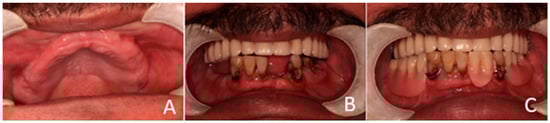

Figure 1. Preoperative oral condition. (A) The edentulous maxilla. (B) Partially edentulous mandible. (C) Maxillary denture and mandibular partial denture.

The clinical dental assessment, at the time, indicated a completely edentulous maxilla and a partially edentulous mandible. The residual mandibular teeth exhibited periodontal compromise, classified as Grade 3 mobility according to the Miller Classification, with multiple cavities and a poor overall prognosis (Figure 1).